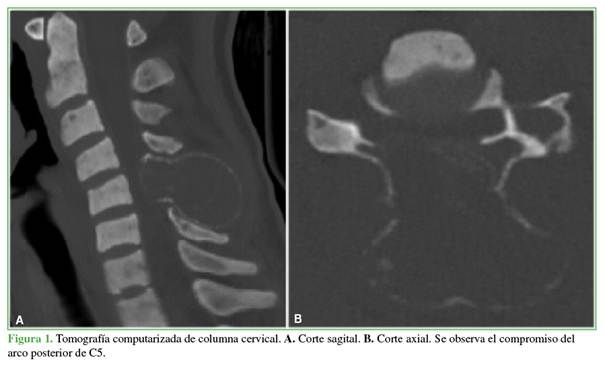

Se solicitaron radiografías y una tomografía computarizada de columna cervical que mostraron una voluminosa lesión osteolítica con márgenes esclerosos en el arco posterior de la 5.a vértebra cervical y extensión a partes blandas adyacentes de dicha región (Figura 1). En la resonancia magnética, se observó una compresión medular severa en la 5.a vértebra cervical (Figura 2).

El tumor pardo, en particular, suele aparecer en la radiografía o el estudio tomográfico como una imagen lítica, multilobulada que puede o no contener márgenes periféricos esclerosos. En la resonancia magnética, se observa una lesión hipointensa en la secuencia T1 e hiper/isointensa en la secuencia T2 con tendencia a la invasión de tejidos adyacentes; cuando se administra un medio de contraste intravenoso suele realzarlo.7,8